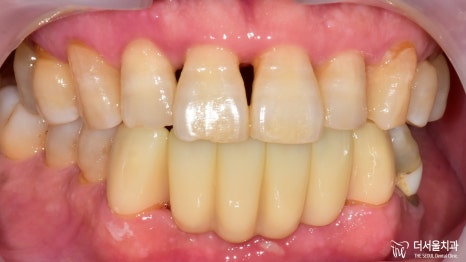

크라운까지 올려드렸습니다.

더 건강하고 멋있는 미소를 갖게 되셨네요ㅎㅎ

임플란트 치과 의 좌측 과정은

최종 보철을 올려드리며 모두 마무리가 되었습니다.

환자께서는 우측 어금니 또한 상실되어 있었는데요.

현재, 우측 식립을 기다리고 있는 중입니다.